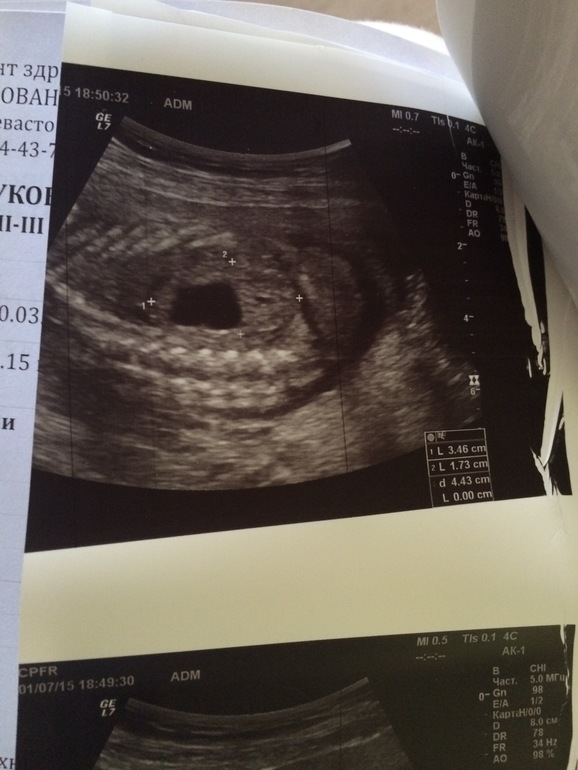

Добрый день. В 20 недель диагностировали на узи удвоение левой почки плода. Лоханка была расширена до 12мм.

в 22 недели было сделано экспертное УЗИ в ЦПСиР.

Там удвоения не нашли, но выдали более ужасное заключение.

Правда сказали. что с 20 по 22 неделю лоханка не увеличилась.

прикрепляю результаты узи в ЦПСиР.